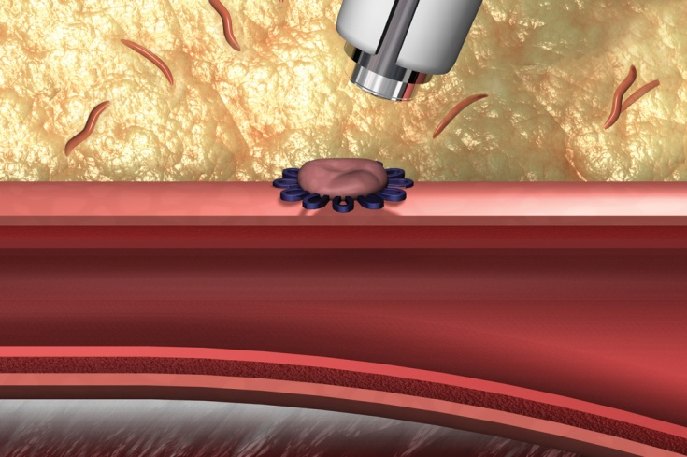

术后穿刺点管理

采用StarClose SE 血管闭合器对股动脉穿刺点进行闭合管理。

整个手术过程很成功,但需要强调的是不能忽视股动脉穿刺点的管理,否则可能会引起血管穿刺点相关并发症的发生,例如:血肿,腹膜后出血,假性动脉瘤等,对患者带来不良愈后。

此次对于股动脉穿刺点闭合采用的是StarClose SE 血管闭合器,原理是采用钛夹血管外夹闭的方式对股动脉穿刺点进行闭合,一期闭合,手术台上即可确定止血效果,其主要优势: 即刻止血,操作简便,在血管内不留任何痕迹,不影响二次穿刺;给临床带来的益处是医生更加放心下手术台,缩短了整体手术时间,减少了导管室工作人员的压力,并发症少减轻了医护人员的护理难度和工作量;对患者而言术后制动时间缩短,减少了血栓的风险,炎症反应小,同时减少需要服用止疼药或插导尿管等的时间,可以提早出院,患者体验好;对科室而言,可提高床位周转率,减少患者住院费用。重视穿刺点的管理操作,有时候给临床带来的获益良多!